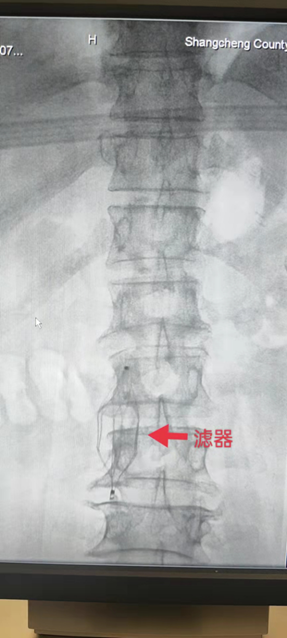

为保障患者的安全,陈锴剑医师立即申请多学科会诊,经神经内科周百武主任团队为孙阿姨查体会诊后认为,孙阿姨的下肢静脉血栓已形成,操作部位有血栓存在,手术中因挤压等原因有血栓脱落导致肺栓塞的可能,必须行下腔滤器置入术。在与孙阿姨及家属充分沟通介入手术利弊及相关风险、费用,并签署手术知情同意书后,神经内科介入团体制定了缜密的手术方案。3月29日,在介入导管室,刘丽副主任医师组织介入团队独立为患者完成下腔静脉滤器置入术,手术过程顺利,用时仅15分钟,术后患者无不适症状,生命体征平稳,达到了预防急性肺栓塞的作用,为孙阿姨次日的骨折固定术的顺利打下了坚实基础,保障了她的安全。

下腔静脉置入术指的是通过股静脉或者颈静脉进行穿刺,插入静脉导管,然后把特殊的过滤器放置到下腔静脉,用来过滤通过下腔的脱落血栓,主要用于下腔静脉血栓、髂静脉血栓和下肢深静脉血栓等疾病治疗,可以防止血栓进入心脏,造成肺动脉栓塞等不良后果。